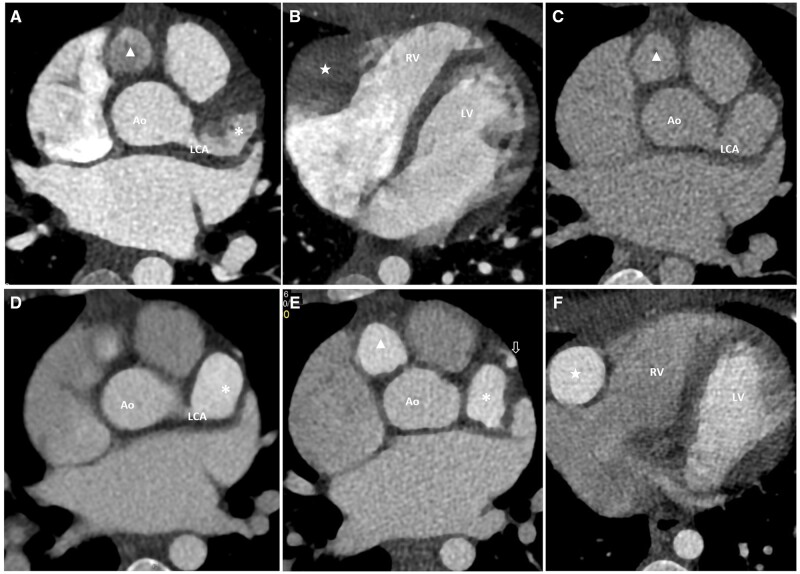

Kawasaki disease is the most common vasculitis causing acquired coronary artery aneurysm (CAA) and affects mostly children. Computed tomography coronary angiography (CTCA) has unique diagnostic and prognostic values in cases of giant CAA. Here, we report technical challenges encountered when performed CTCA for a case of Kawasaki disease complicated with giant CAA. In particular, there was significant flow alteration caused by the giant CAA(s) causing suboptimal enhancement when the standard protocol was applied. We share our experience in optimizing the scan and propose the use of either manual bolus tracking or test bolus technique in similar scenarios, as well as multidisciplinary approach to optimize patient preparation.